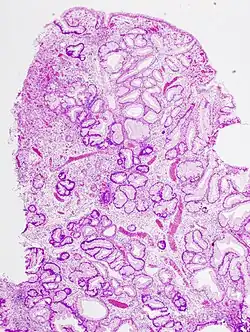

W przypadku polipa zapalnego pierwotnie dochodzi do odczynowego rozrostu składnika łącznotkankowego podścieliska, a wtórnie do rozrostu składnika nabłonkowego. Szczególną postacią polipów zapalnych są polipy regeneracyjne, w których dochodzi do nadmiernego rozrostu błony śluzowej, jako reakcji na jej zniszczenie. W polipach nowotworowych rozrost pierwotnie dotyczy nabłonka, a wtórnie wciągane jest podścielisko łącznotkankowe. Niektóre gruczolaki polipowate (zwłaszcza jelita grubego) mogą przekształcać się w gruczolakoraki.

Polipy uszypułowane (posiadające rodzaj „nóżki”) jest stosunkowo łatwo usunąć w trakcie badania endoskopowego przy pomocy pętli, natomiast polipy o szerokiej podstawie zwykle są przed usunięciem obstrzykiwane. Badanie endoskopowe, wyskrobiny są najczęstszymi zabiegami diagnostycznymi mającymi na celu pozyskanie tkanek polipa celem ustalenia jego postaci i etiologii przy pomocy badania mikroskopowego. Należy dążyć do tego aby podczas biopsji usunąć możliwie jak największą masę polipa, a zwłaszcza jego szypułę. W przypadku polipów nowotworowych, jeśli w obrębie jego szypuły znajdowany jest naciek raka, niezbędne bywa szybkie poszerzenie zabiegu (wycięcie danego narządu w granicach zdrowych tkanek).